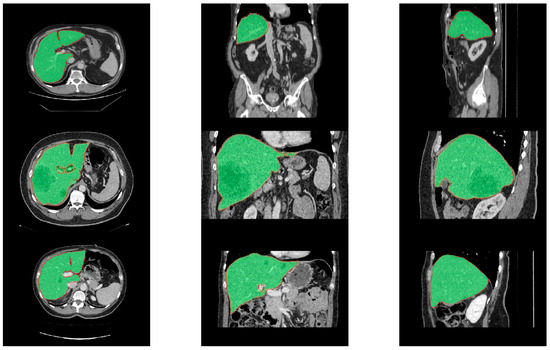

4.6. Segmentation Results of the Proposed Model